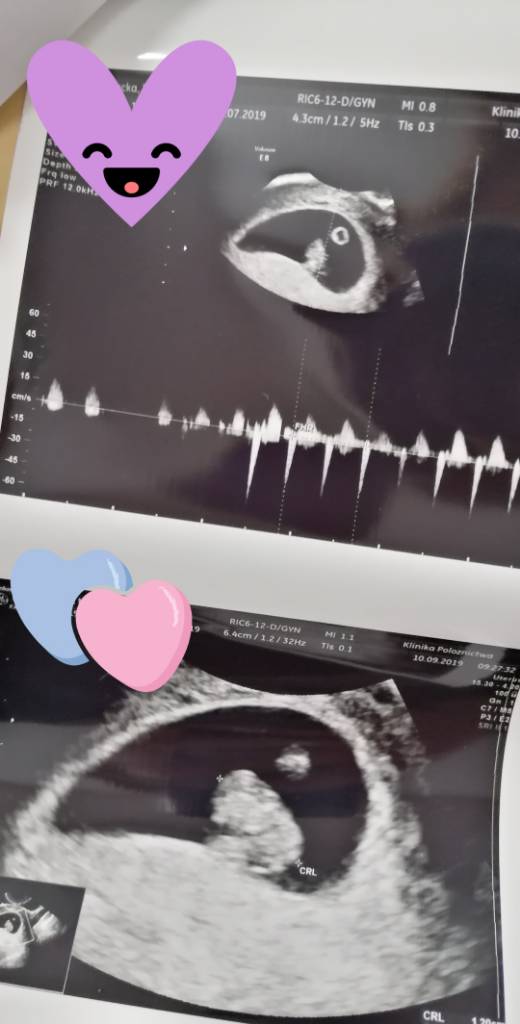

A ja Wam przedstawiam moja Fasolke. Serduszko biło 144 uderzeń na minutę

różnica z OM i USG się wyrównuje bo z OM 7+6 a wg USG 7+3

Robaczek urósł, CRL ostatnio wynosił 0,34 a teraz 1,20, tydzień różnicy

Zobacz załącznik 1020742